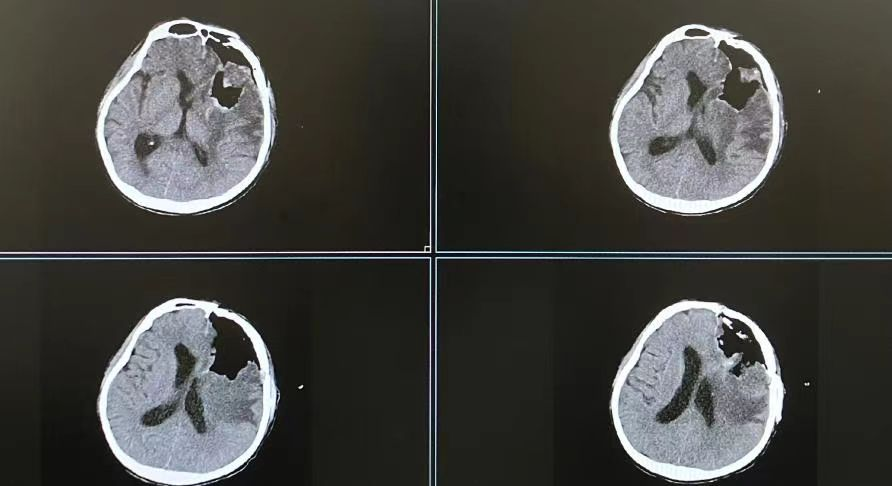

2023年的8月份,31岁的潘先生突发意识模糊,呼之不应,小便失禁,紧急送到我院诊治。行头颅CT提示:左侧额颞叶囊实性占位性病变并出血,头颅MRI提示:考虑额叶胶质瘤,大脑镰下疝形成。潘先生颅内的肿瘤直径达到70mm,肿瘤体积大,恶性程度高,又侵犯与肢体运动密切相关的脑功能区。

患者术前头颅MRI